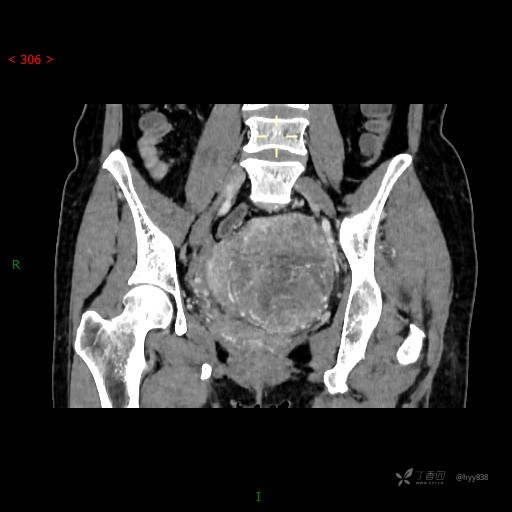

辅助检查:CT

盆腔CT平扫

增强动脉期

静脉期